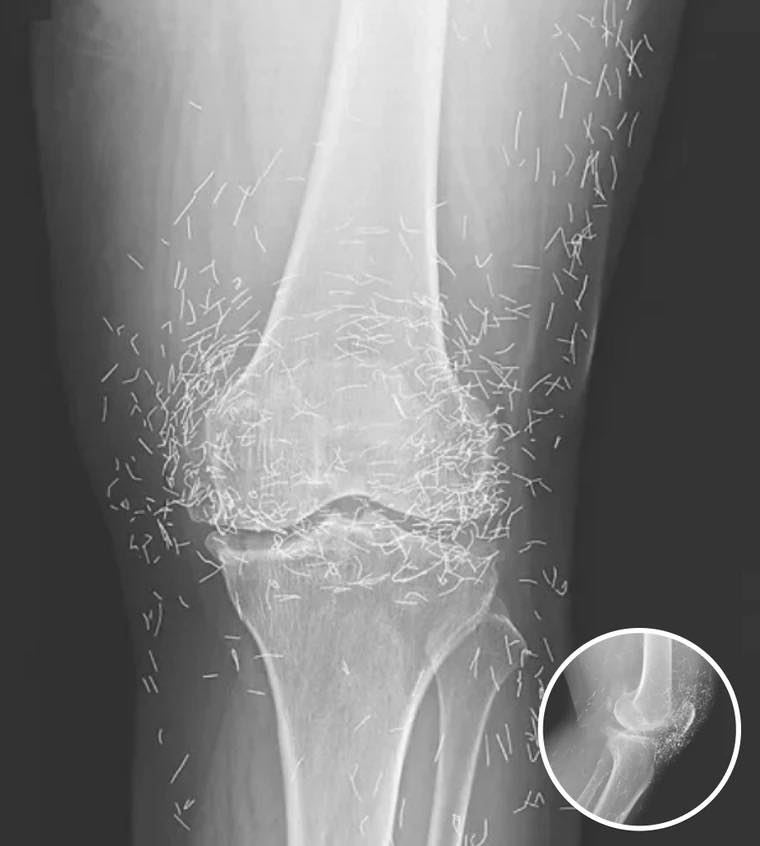

A 65-year-old woman in South Korea experienced a shocking medical discovery when doctors found hundreds of tiny gold needles embedded in her knee tissue during a routine X-ray. She had been suffering from chronic osteoarthritis, a condition that causes joint pain, stiffness, and inflammation due to cartilage breakdown.

In this case, the needles were intentionally left in her body as part of a long-term treatment strategy. Some practitioners believe that leaving gold needles or threads in place can provide ongoing stimulation to the affected area. However, medical professionals warn that this approach carries significant risks.

Dr. Ali Guermazi, a radiology expert from Boston University not involved in the case, explained that the human body can react negatively to foreign objects. Inflammatory responses, tissue damage, and infections are potential complications. Additionally, the embedded needles can interfere with medical imaging, making diagnosis more difficult.

One of the most serious risks comes with MRI scans. The powerful magnetic forces used in MRIs can cause metal objects to move within the body, possibly leading to punctured blood vessels or other life-threatening injuries. This makes metal implants a critical concern for patients who may need future imaging.